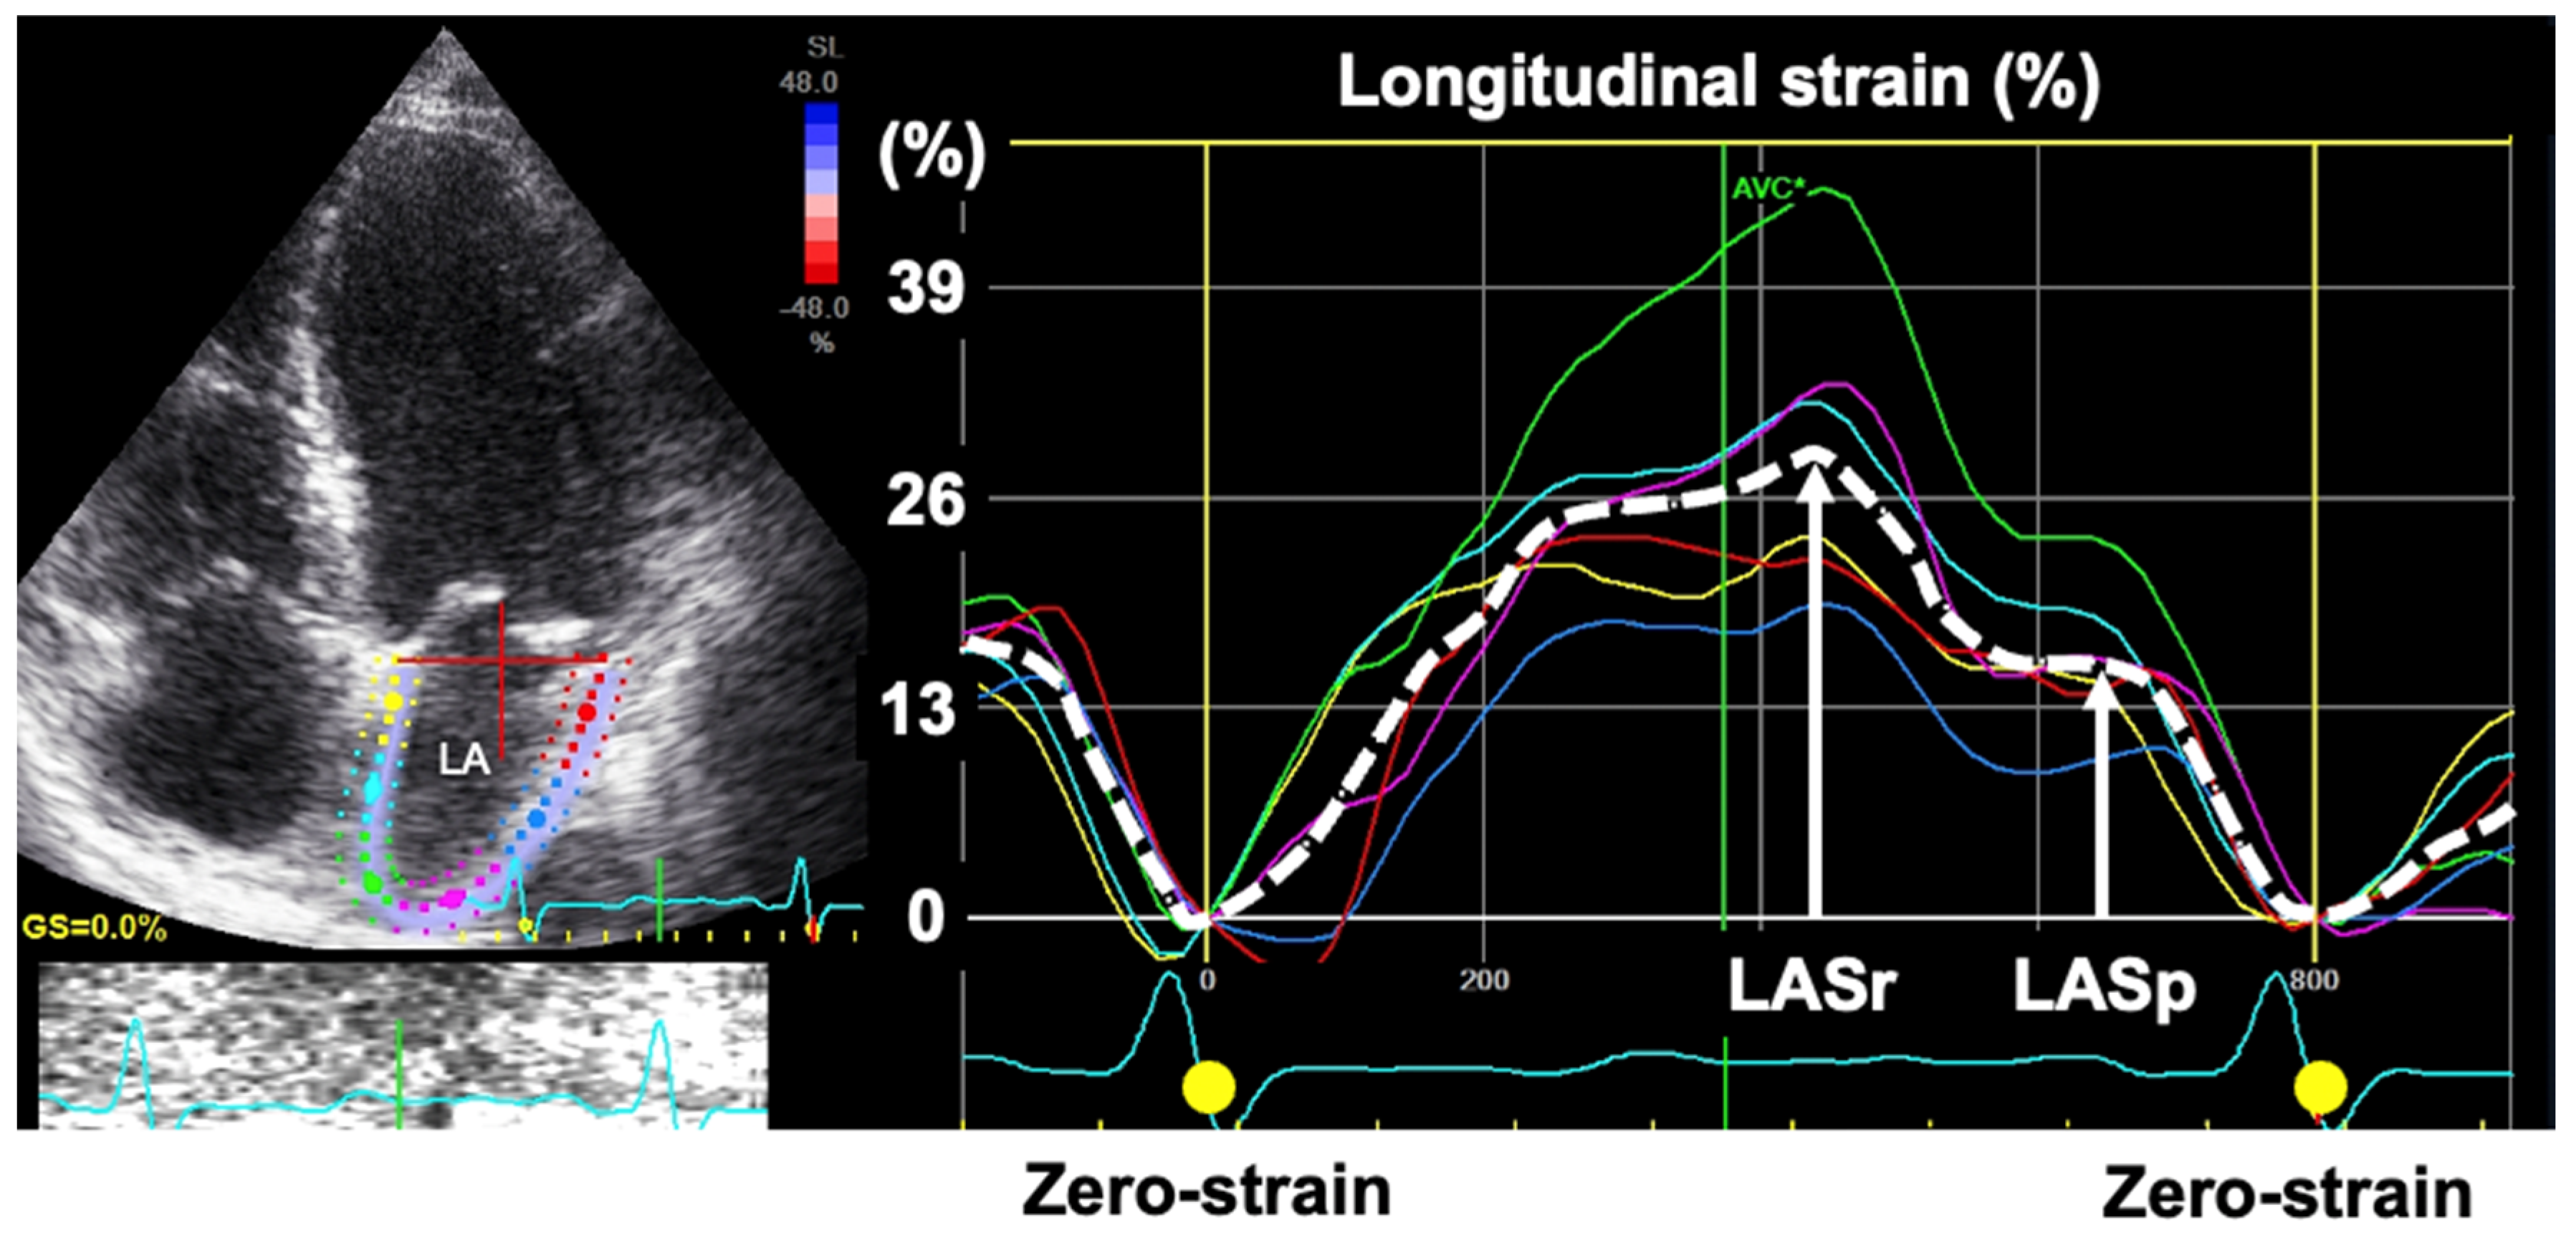

- Badano, L.P.; Kolias, T.J.; Muraru, D.; Abraham, T.P.; Aurigemma, G.; Edvardsen, T.; D’Hooge, J.; Donal, E.; Fraser, A.G.; Marwick, T.; et al. Standardization of left atrial, right ventricular, and right atrial deformation imaging using two-dimensional speckle tracking echocardiography: A consensus document of the EACVI/ASE/Industry Task Force to standardize deformation imaging. Eur. Heart J. Cardiovasc. Imaging 2018, 19, 591–600. [Google Scholar] [CrossRef]

- Inoue, K.; Khan, F.H.; Remme, E.W.; Ohte, N.; Garcia-Izquierdo, E.; Chetrit, M.; Monivas-Palomero, V.; Mingo-Santos, S.; Andersen, O.S.; Gude, E.; et al. Determinants of left atrial reservoir and pump strain and use of atrial strain for evaluation of left ventricular filling pressure. Eur. Heart J. Cardiovasc. Imaging 2021, 18, 61–70. [Google Scholar] [CrossRef]